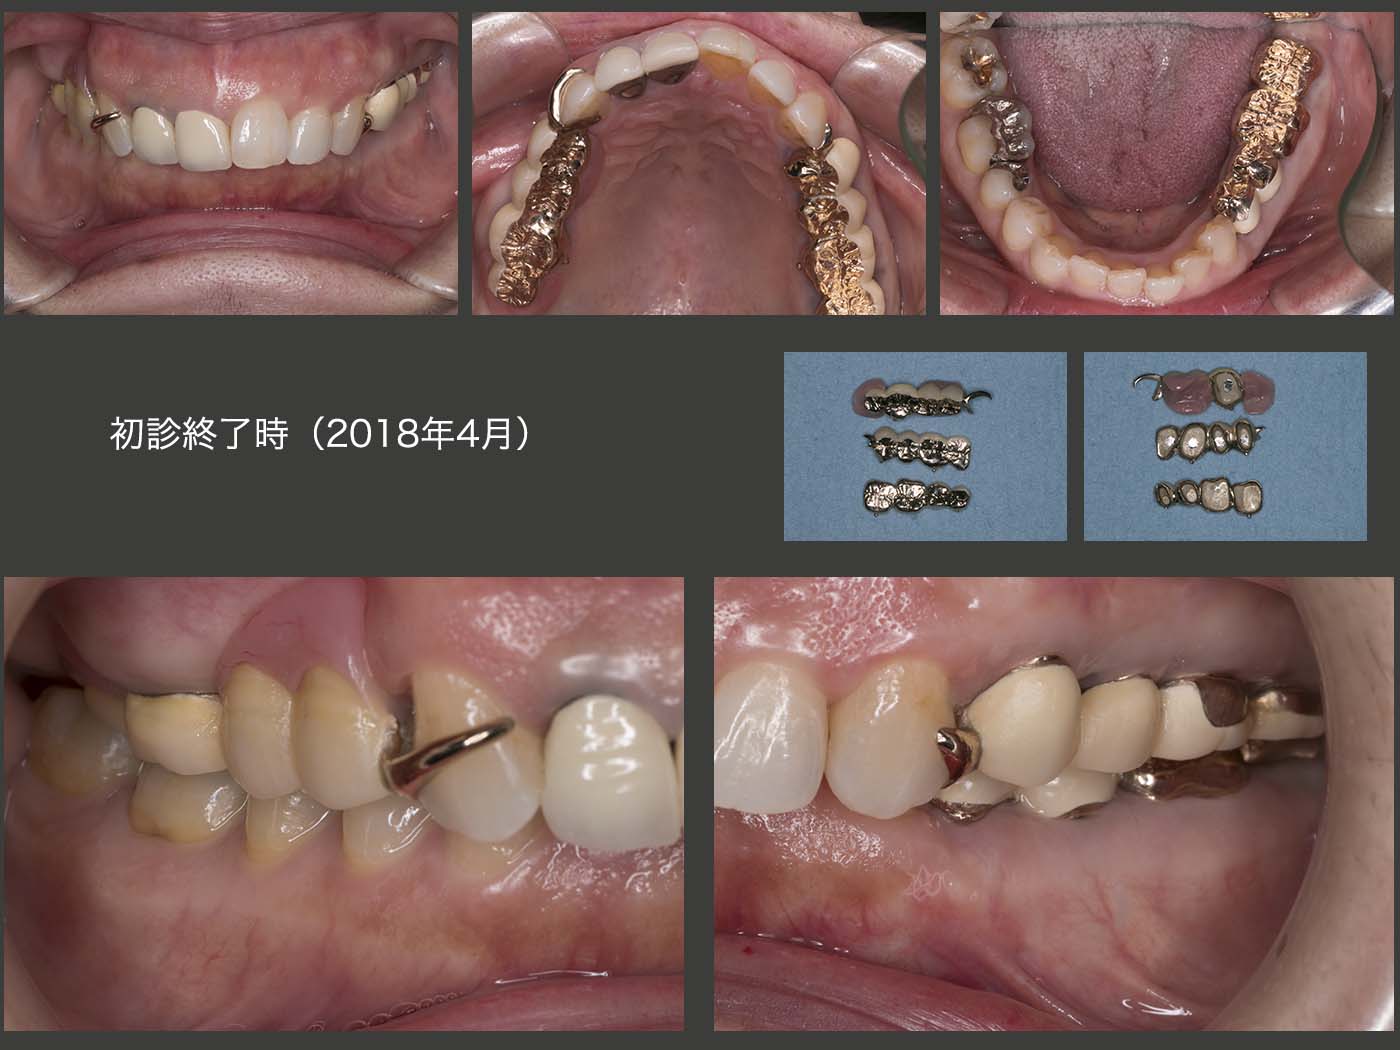

2018年4月,初診終了時の状態.右上については,即時義歯のままでも構わないが,咬合高径がない分,支台装置をくるむレジン量が少ないことが危惧された.そこで,義歯の破折を予防するために,さらに強固な義歯に作り換えた.(咀嚼の中心は左側のため,右側の義歯の破折は生じにくい.少々オーバートリートメントの感は拭えない.)

義歯を装着した状態.上下左側の個々の歯は当初条件が悪かったが,連結固定したことで咬合・咀嚼力に対応でき,また左側の咬合支持を強固に得られたことは,今後の経過によい影響を及ぼすであろうと期待している.ただ,左側の偏咀嚼および咬み過ぎによる歯根破折の問題もあるので,意識して右側でも咀嚼して貰うこと,また,あまり硬いものを左側で咬まないようにお願いしている.